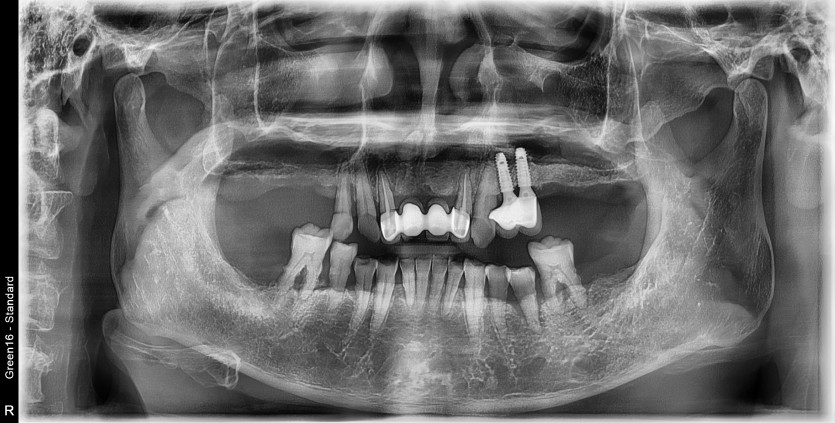

만 60세 상악 전체 임플란트 증례(기존 임플란트 활용)

상악 전체 임플란트 증례입니다.

(타원 임플란트 활용)(하악 일부)

12개의 임플란트로 완성하였습니다.